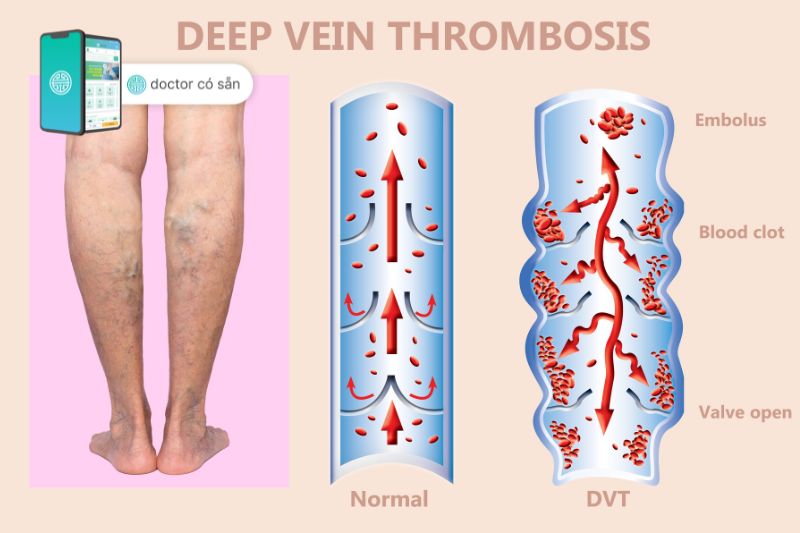

- Huyết khối tĩnh mạch sâu: Bất kỳ phẫu thuật nào ở chân đều làm tăng nguy cơ hình thành cục máu đông trong tĩnh mạch chân. Cục máu đông có khả năng di chuyển theo dòng máu đến phổi gây thuyên tắc phổi và đe dọa đến tính mạng.